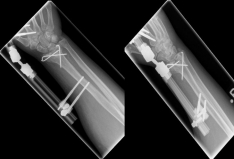

Pictures: In this case, the articular surface of the wrist was completely destroyed, so that only a therapy by means of outer retainer and some K-wires to correct the position was possible. Here is a practice only after removal of the outer holder after 6-8 weeks possible. Such severe joint injuries often lead to premature joint wear